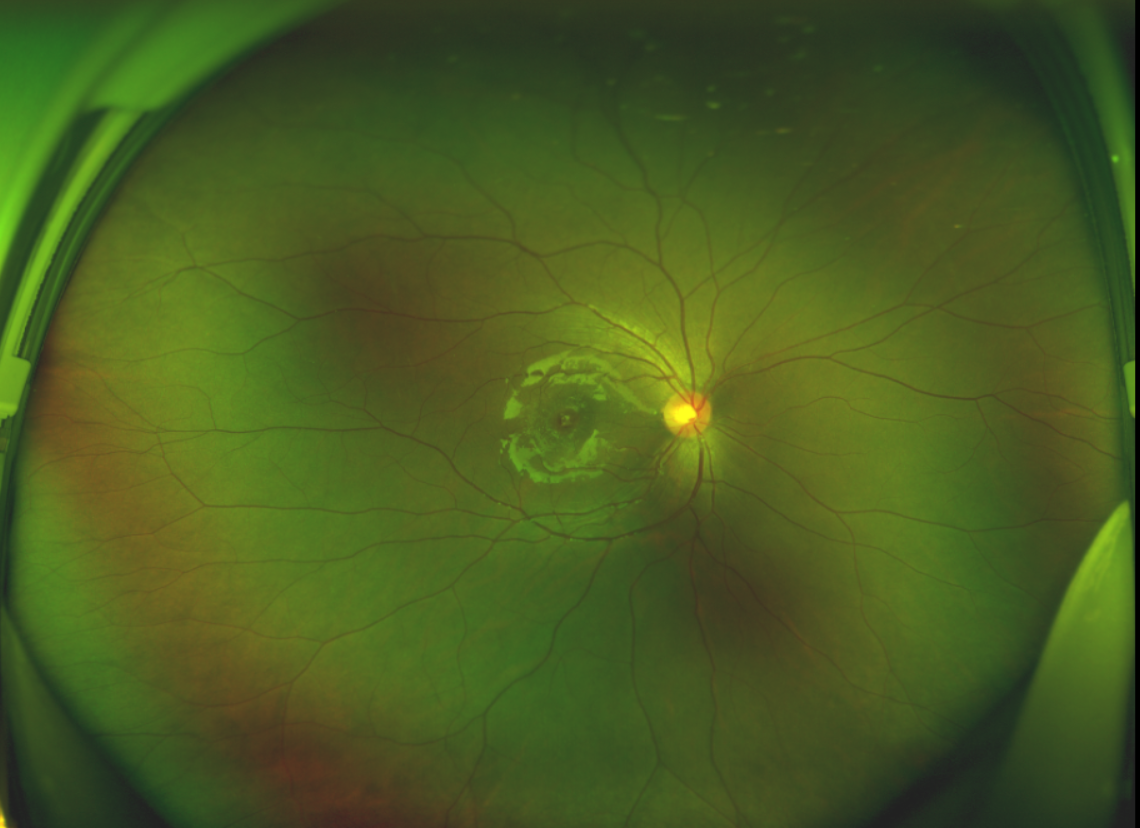

半年前的一次意外,誠(chéng)誠(chéng)(化名)右眼不慎受傷導(dǎo)致黃斑裂孔。從此,他的“視”界不再清晰,也不再有直線條……

黃斑位于視網(wǎng)膜正中心,是視覺(jué)最敏銳的區(qū)域,堪稱“眼底的心臟”,負(fù)責(zé)我們閱讀、駕駛、識(shí)別人臉等精細(xì)視覺(jué)。 當(dāng)黃斑區(qū)的神經(jīng)組織出現(xiàn)全層缺損,形成一個(gè)“孔洞”,即為黃斑裂孔,它會(huì)直接導(dǎo)致中心視力急劇下降、視物變形、視野中心出現(xiàn)暗區(qū)。

由于裂孔較小,當(dāng)?shù)蒯t(yī)院建議先觀察,看看裂孔是否能夠自愈??砂肽陼r(shí)間過(guò)去了,誠(chéng)誠(chéng)傷眼的裂孔不僅沒(méi)有愈合的跡象,反而越來(lái)越大,這讓家長(zhǎng)的心揪得更緊了。

經(jīng)過(guò)詳細(xì)的檢查和評(píng)估,王曉波主任決定采用“內(nèi)界膜翻轉(zhuǎn)覆蓋聯(lián)合粘彈劑固定術(shù)”為誠(chéng)誠(chéng)進(jìn)行治療。